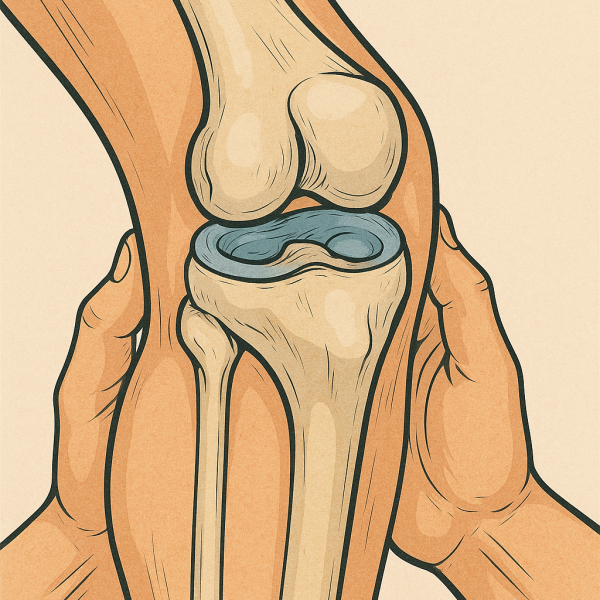

پارگی منیسک زانو

آسیب رایج در ورزشکاران که معمولا به علت چرخش ناگهانی زانو رخ می‌دهد و باعث درد و تورم در زانو می‌شود.

پارگی رباط صلیبی قدامی

یکی از رایج‌ترین آسیب‌های رباط زانو که می‌تواند باعث ناپایداری و کاهش کارایی زانو شود.